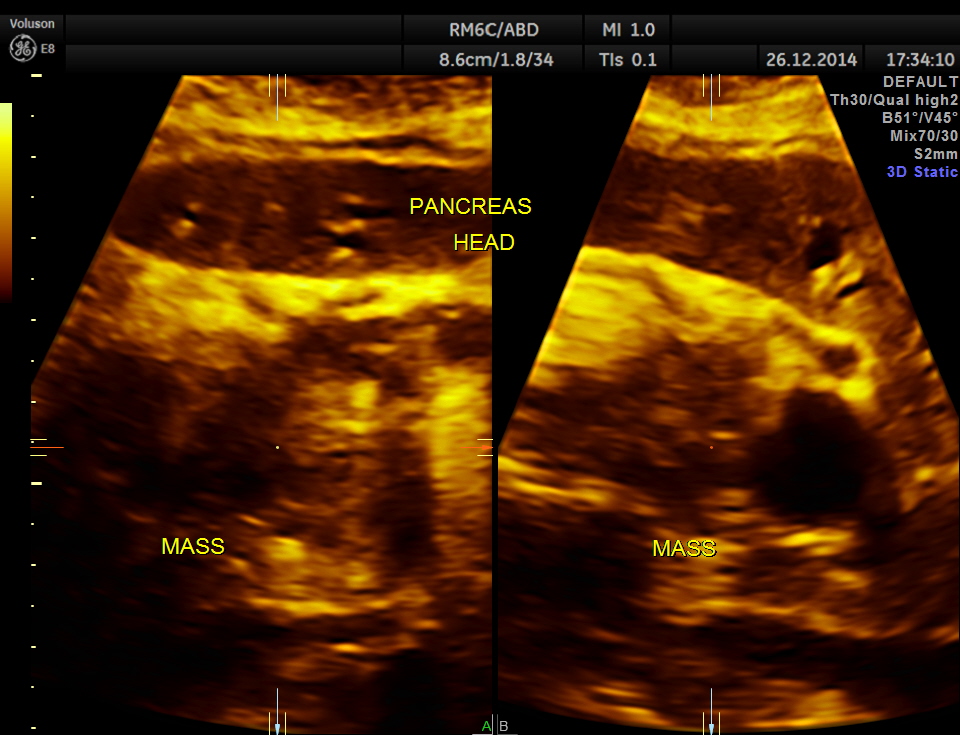

the head region of the pancreas shows an irregular mass lesion

3d reconstruction of the head of the pancreas